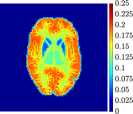

Figure 4, Figure 5, and Figure 6 show the mean images computed over the ten reconstructions obtained by the methods reg-AS-TR, reg-GN, and by the Matlab routine lsqcurvefit implementing a standard Trust-Region-Reflective least-squares algorithm [11, 10]. We used the noise-free IF and the perturbed IF with and of noise, respectively. Figure 7 contains mean and standard deviation values of the kinetic parameters computed over the ten reconstructions and over each one of the four homogeneous regions, for each one of the three noise levels on the IF.

In general, reg-AS-TR and lsqcurvefit seem to provide similar mean reconstructions, although uncertainties associated to lsqcurvefit are significantly bigger. On the other hand reg-GN seems to systematically underestimate the parameter values within region . Furthermore and as expected, for all methods the quality of the parametric reconstructions deteriorates with increasing noise levels; this is more clear from the and parametric images, probably due to the different sensitivities of the data with respect to the model parameters [37]. In reg-GN and lsqcurvefit some artifacts can be observed at the edges of the homogeneous regions, especially around region and region , whereas the effect of regularization in reg-AS-TR results in a reduced presence of artifacts while the structure of the regions is preserved. This general trend is confirmed by the error-bar plots of Figure 7. Finally, the frames in Figure 8 corresponding to reg-AS-TR show a significant improvement of the image quality with respect to what is provided by the other two approaches.